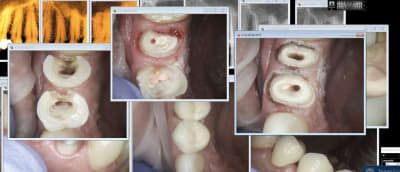

Encore 2 zigouigouis.

Capture d écran 2018 07 16 16.46 - Eugenol

Bon sur ce coup j'ai joué du laser.

Capture d écran 2018 07 16 16.50 - Eugenol